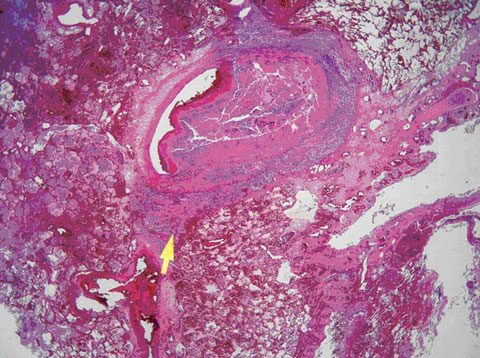

Postmortem examination showed that the principal pathology lay in the lungs and myocardium. The lungs showed multiple foci of bronchopneumonia, many coalescing to form extensive areas of lobar pneumonia. However, the most striking feature seen on histology was involvement of the pulmonary vasculature by staphylococcal septicaemia. Staphylococci had invaded the walls of multiple blood vessels, producing a florid vasculitis with subsequent secondary thrombosis of the involved vessels (Figure). This process involved both large and small vessels to such an extent that a lethal degree of bilateral arterial thrombosis had developed. The larger thrombosed vessels were obvious at macroscopic examination of lung slices. Multiple small thrombi were seen on microscopy. The myocardium showed focal abscesses containing staphylococcal colonies. Adjacent myocardial fibres showed necrosis, which correlated with the patient’s raised troponin level. The other organs of the body were remarkably free of sepsis, the spleen was normal, and the spinal column showed no evidence of osteomyelitis. A furuncle on the left elbow was confirmed.